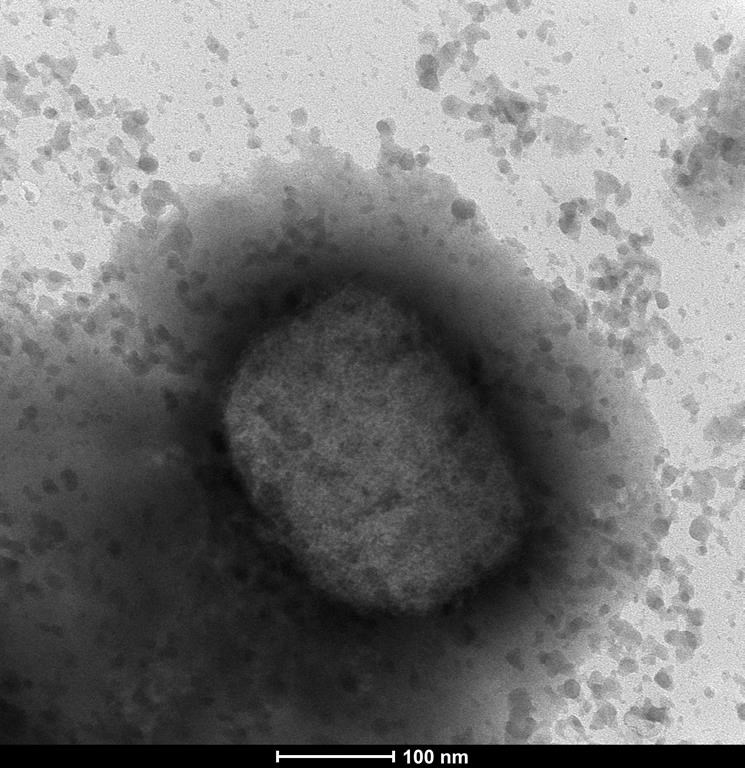

La maladie provient de la même famille de virus qui causent la variole, que l'Organisation mondiale de la santé a déclarée éradiquée dans le monde en 1980. Les vaccins contre la variole se sont avérés efficaces pour combattre le virus.